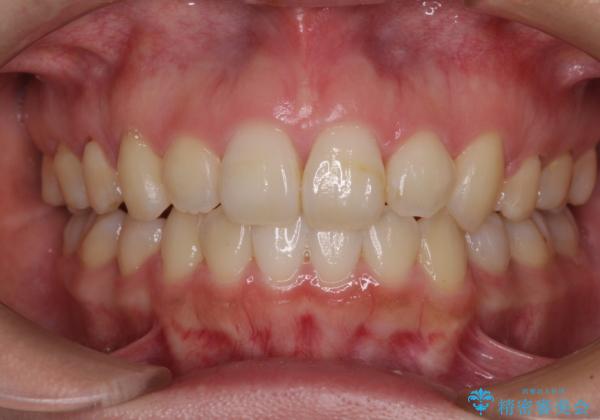

- 口元の突出感を気にして来院された患者様です。

診断の結果、上顎左右第一小臼歯4本抜歯により、叢生を解消するとともに口元を引っ込めていくことが望ましいと判断しました。

抜歯矯正による口元の改善にはワイヤー矯正が望ましいのですが、ダンサーとしての仕事を行っているため、インビザラインにて治療を行うこととしました。

インビザラインによる矯正治療は、どれだけマウスピースを外す時間を短くできるかが成功の鍵となりますが、抜歯矯正ではよりシビアに要求されます。

こちらの患者様は、1日22時間以上を厳守してくださり、3年強で終えることができました。